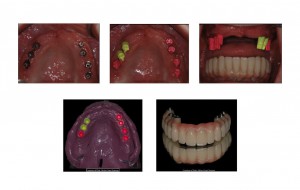

"Il vantaggio di applicare un full arch correttamente in tutti i suoi aspetti si rivela nell'applicarlo senza ritocchi a un paziente al quale è terminato l'effetto dell'anestesia. E' in quel momento che un sistema d'impronta valido come il SOL mostra differenza rispetto ad altri. Se poi questo sistema è comodo per improntare, tanto di guadagnato. Inoltre se il mio paziente manifestasse ipersensibilità nei confronti dei materiali per impronta, gli libero la bocca in tre secondi e riduco il cucchiaio". Dott. Ezio Zandanel -